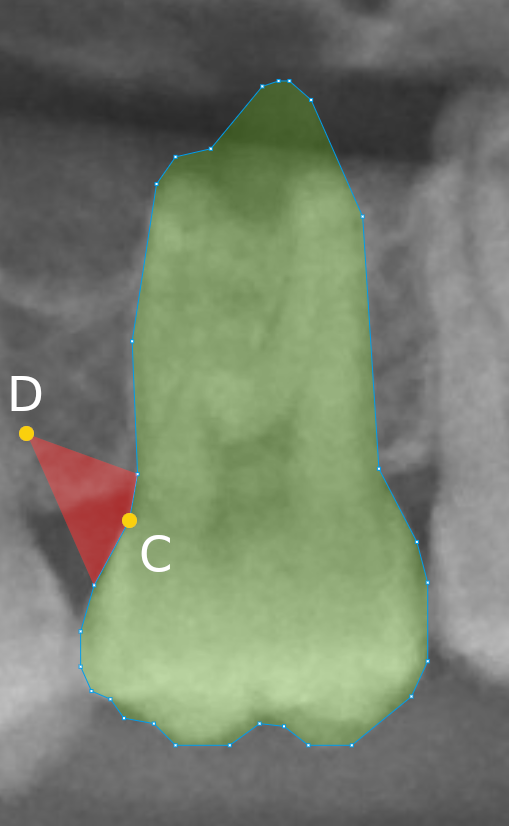

Refer to caption

(a) Original code.

(b) Changed code.

Figure 5: Illustration of the software visualization due to the code changes. The red area evinces the higher impact in the annotation when on a point shift. We reduced the shape opacities, easing the annotation verification, and lowered the number of control points. (a) Visualization of a tooth annotation with the original code and no tolerance in the Ramer–Douglas–Peucker algorithm and the impact on the annotation when point A moves to point B. (b) Visualization of a tooth annotation with the changed code and the impact on the annotation when point C moves to point D.

The HITL-based labeling started with the predictions of the HTC neural network. We labeled 450 radiographs in the first HITL iteration, as indicated in Figure 4. This iteration was considered experimental, as the annotators had not previously verified annotations from model predictions. Indeed, it quickly became notorious that manual image labeling is quite different from labeling verification. When labeling a radiograph from scratch, the annotator may promptly detect or localize the teeth and segment their instances using the annotator software mechanisms such as the polygon or brush tools. In the COCO Annotator software, the resulting area is filled with a colored layer to distinguish the already segmented objects from the others. On the other hand, when working on verifying neural network predictions, the human annotators must visually inspect the results and quickly confirm or correct the provisional labels. For that, the annotators can benefit from any software annotation tools, but in our case, they most frequently used the polygon point drag-and-drop feature. Two issues arise from this: (i) the filled segmented areas obstruct the instances, hampering the verification; (ii) the large number of points per segmentation slows down and hardens the corrections because point shift has less impact on the annotation. We mitigated these issues by changing the software source code, reducing the shape opacity, and lowering the number of control points through the Ramer–Douglas–Peucker algorithm with a tolerance of 2 pixels (Douglas and Peucker, 1973). Figure 5 illustrates these modifications, evincing the new higher impact of point shift. Furthermore, we added a keyboard shortcut to toggle the annotation visualization, which was very helpful for the annotators.